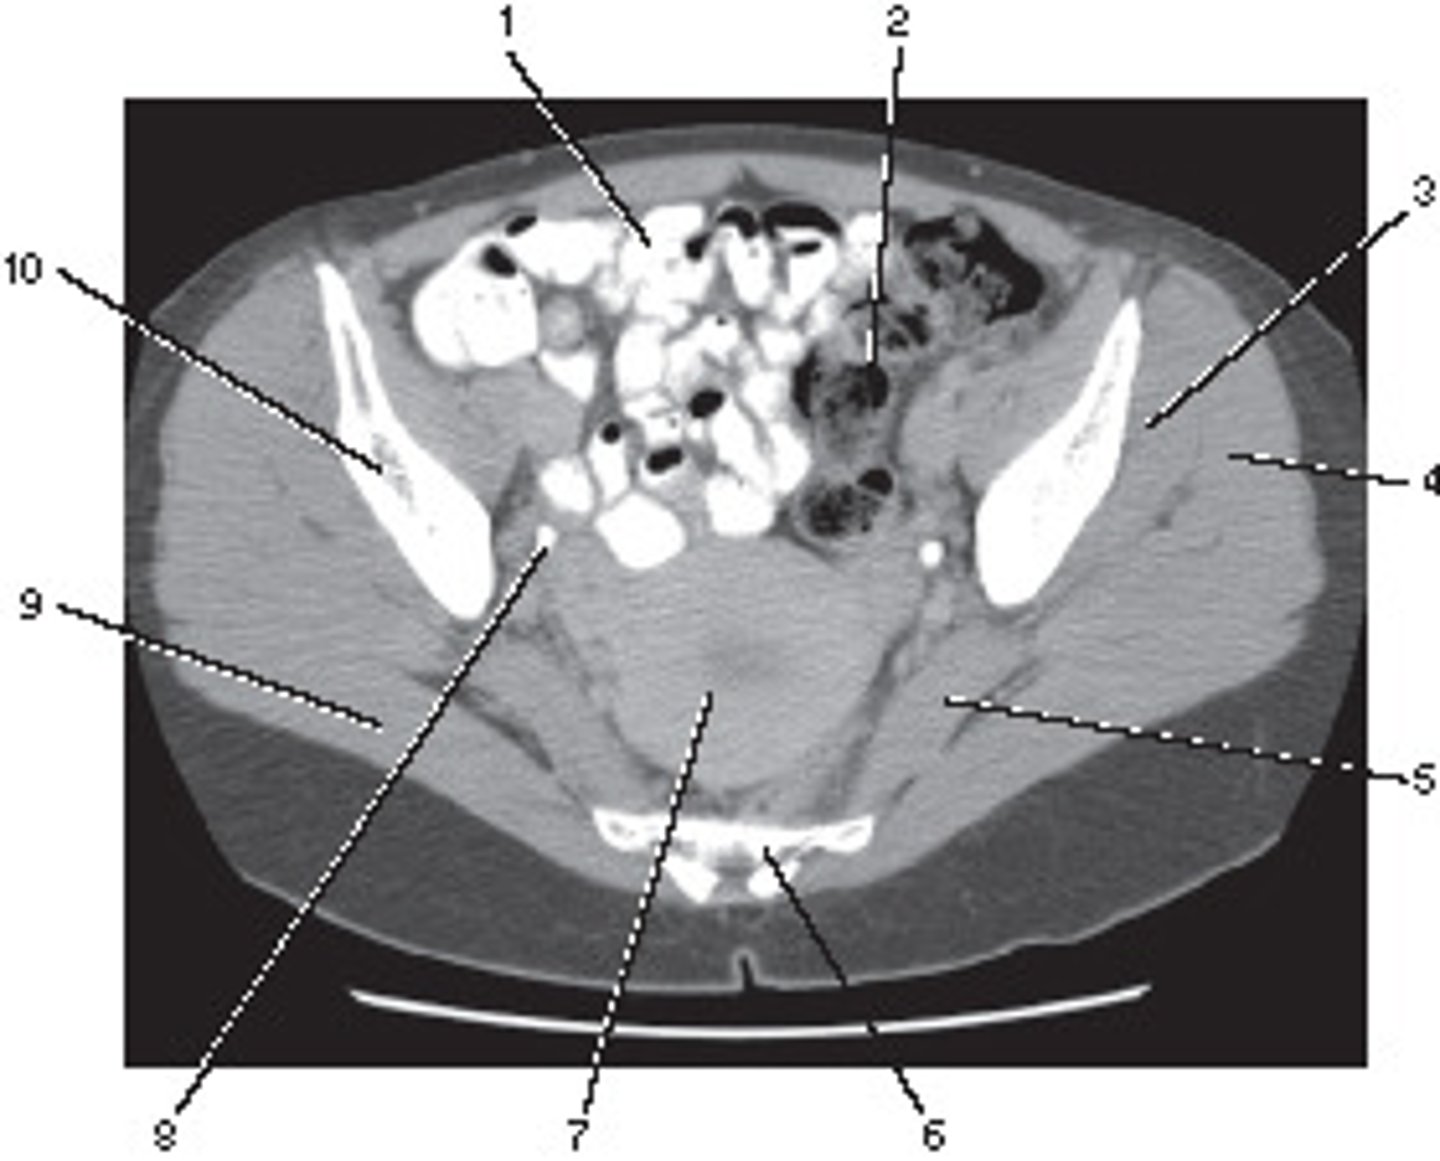

Axial

This image displays what anatomic plane?

<p>This image displays what anatomic plane?</p>

Ileum

Number 1 corresponds to which of the following?

<p>Number 1 corresponds to which of the following?</p>

Ilium

Number 4 corresponds to which of the following?

<p>Number 4 corresponds to which of the following?</p>

Femoral Artery

Number 2 corresponds to which of the following?

<p>Number 2 corresponds to which of the following?</p>

Ureter

Number 8 corresponds to which of the following?

<p>Number 8 corresponds to which of the following?</p>

Femoral Vein